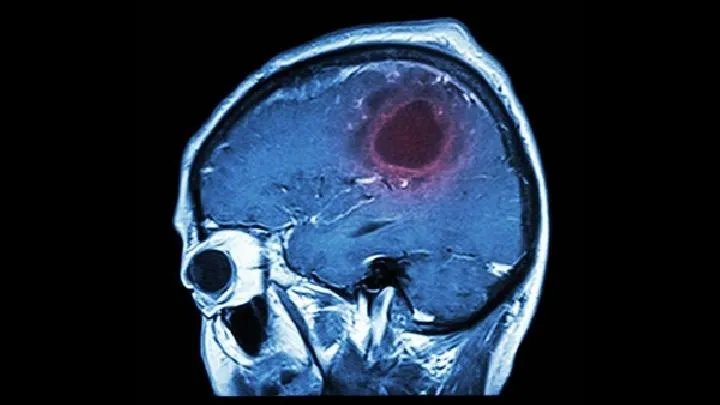

三、心肌梗塞,血栓形成会堵塞血管,此时心肌完全缺血,缺血部位出现心肌坏死,进而导致猝死。实践告诉我们,长期冠心病患者血管狭窄、硬化、反复发作的心肌缺血不能满足需要,反而在周围重新生成新生血管,这些人心梗的死亡率反而比较低,而没有接受治疗、还不知道自己有冠心病的中年人心梗死亡率更高。